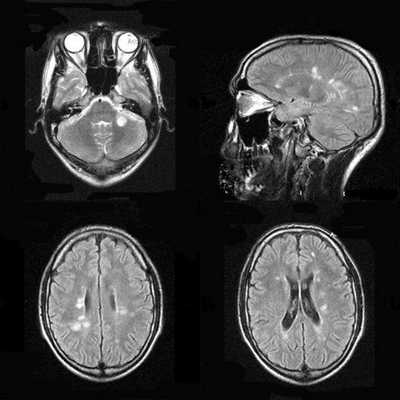

С рождения наблюдалась везикулезная сыпь в области лба. На аксиальной Т2-взвешенной томограмме определяется «missing cortex» симптом: потеря нормального изменения сигнала от коры (кора и белое вещество неразличимы) в обеих затылочных областях, больше слева.

Т1-взвешенная аксиальная томограмма: диффузная кистозная энцефаломаляция с компенсаторной вентрикуломегалией